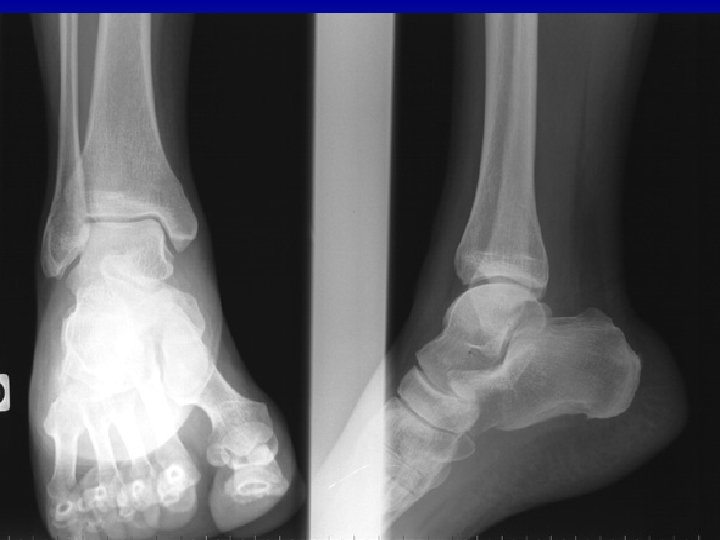

Cheville : quels clichés standard ? n Bilan radiologique: 3 incidences n « face + profil classique » (comparatif chez enfant). n « face rotation interne 20 ° » = incidence de mortaise: malléoles dans le plan frontal, visualise le dôme du talus, recherche de diastasis bimalléolaire (lésion tibio-fibulaire inférieure). n But de l’imagerie à ce stade: Diagnostiquer ou Eliminer une fracture n Recher une lésion associée n

La radiographie standard Dans la pathologie sportive de la cheville n n C ’est la 1ère étape obligatoire dans l ’exploration de la pathologie sportive de la cheville et du pied 3 incidences de bases n Recherche de fractures (fatigue +++), n d ’avulsions, de luxations Recherche de corps étrangers Recherche de « prédisposition » n n Les clichés dynamiques ont un intérêt sur une cheville indolore